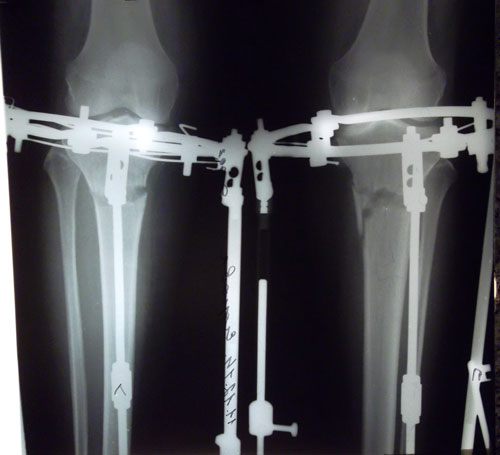

Рентген в 121 день. Снимать аппараты рановато, ждём ещё месяц. Делаем повторный рентген и смотрим. Можно снимать не 10 апреля, а на несколько дней раньше. кушайте творог, мясо, кальций, холодец, мумиё (как учили в клинике) и позитивное настроение! 04000000.

Рентген перед снятием аппаратов.

в аппаратах пред снятием.